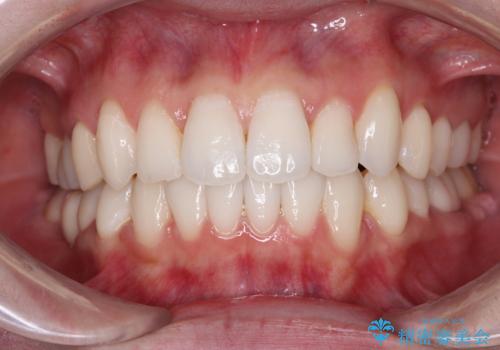

ワイヤー矯正後の後戻り 出っ歯を治したい マウスピース矯正